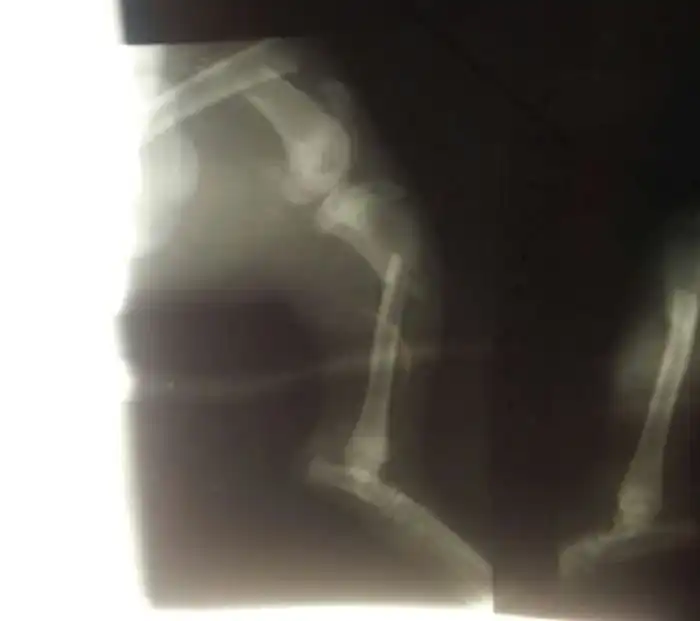

Когда пса доставили в лечебницу, ветеринары предложили его усыпить, однако, фонд настоял на проведении операции. Собаке, которой дали кличку Пират, в семи местах переломало задние лапы, кроме того у нее был сломан крестец. За саму операцию, которая длилась 8 часов, клиника выставила счет в размере 15 000 рублей. Операцию делали в долг, пока на счет фонда поступали деньги от пользователей интернета.